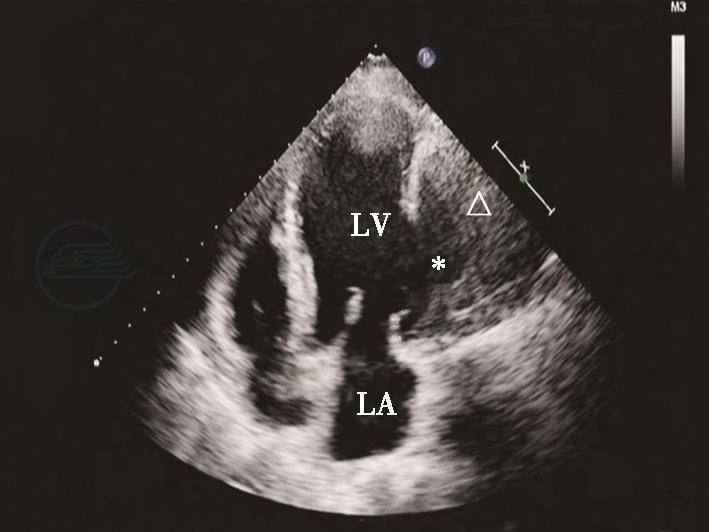

图2心肌梗死后左心室游离壁破裂合并假性室壁瘤形成二维切面图像

心尖四腔心切面显示左心室侧壁破裂形成巨大假性室壁瘤(星号示),其内可见附壁血栓(三角示)。LA.左心房;LV.左心室。